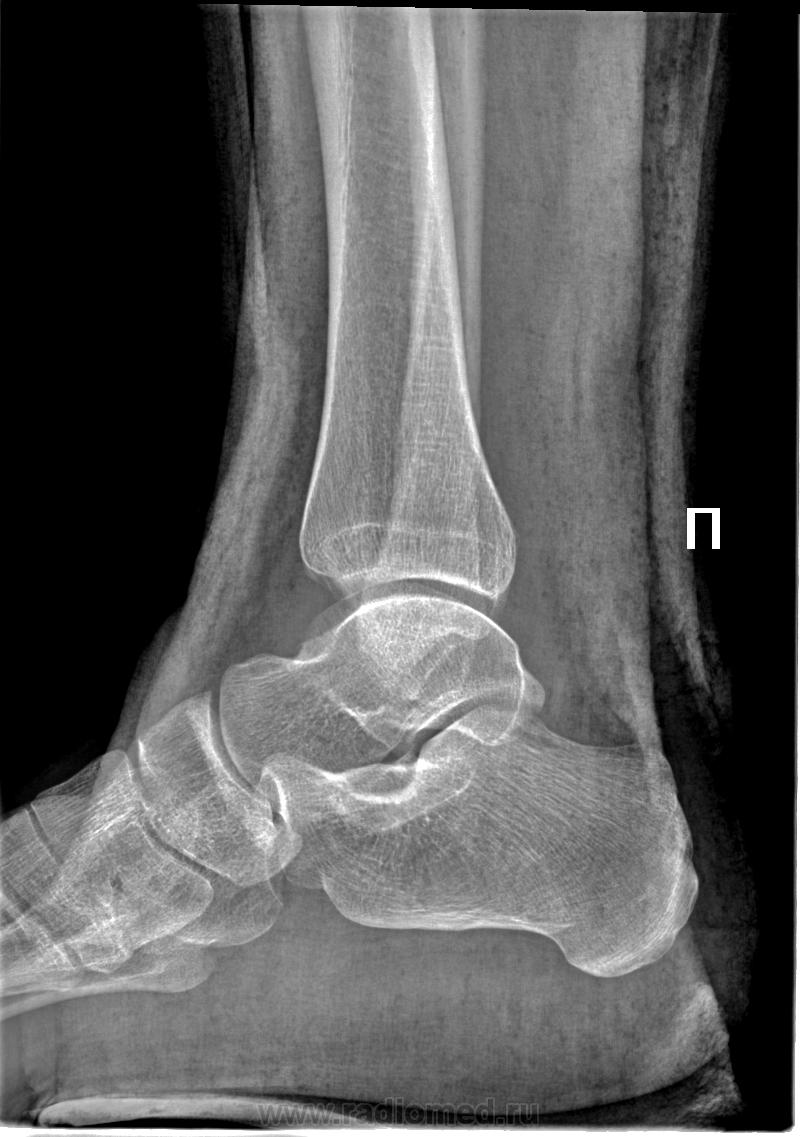

На мой взгляд, это похоже на болезнь Диаза. Интересное наблюдение!

Ранее с подобным не сталкивался ( или не писал, т.к. пишем насколько знаем).

Что за тенюха?

Это на нашей пленочной классике - вуаля! (vega ©), а на этой цифре - не кажется контурообразующим краем. Похоже на кортикальный осколок (тут капсула крепится). Тем более виден на обоих снимках. По таранной- согласен с постом №1, т.к. деформация (импрессия) кортекса имеется и на первичном и на контрольном снимке, вряд-ли некроз.

Verum plus uno esse non potest.